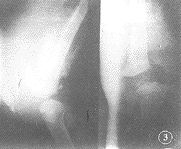

1998-03月摄片示左股骨远侧骨骺内侧增大,外侧变小,呈楔形,胫骨近端骨骺外1/2发育不良。关节腔外侧及髌骨上方斑片状钙化影,左膝关节软组织肿胀,右膝关节未见异常(图2)。同年6月因外伤后左膝及大腿明显增粗,肿胀,行走困难,又行X线检查:左膝关节正侧位片示:左股骨下端骨膜反应,且见大量骨痂广泛包绕骨干,骨骺移位于干骺端前内侧,股骨干骺端与胫腓骨形成关节。髌骨前移,膝关节以上软组织肿胀(图3)。右上肢正位片:右肱骨未见异常,右尺桡骨略缩短,且见尺骨近端和桡骨远端粗大。右下肢正位片:右股骨、胫腓骨未见异常。双手正位片:双手食指末节指骨咬伤后缺如,余未见异常。

图3 与图2相隔3个月,左股骨下端及胫骨上端骨骺均碎裂,干骺端广泛骨膜增生,髌骨前移